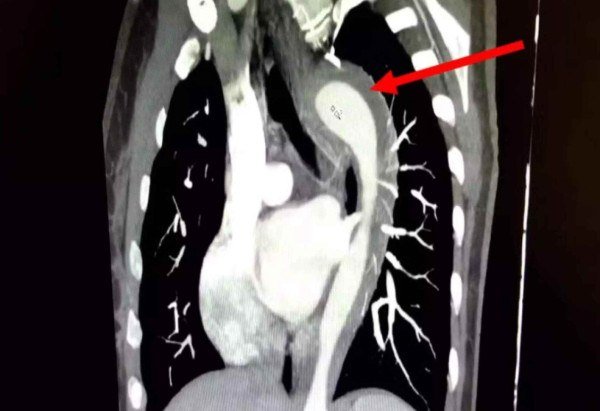

"A dor era intensa e se assemelhava a facadas, associada à falta de ar e náuseas", detalha a paciente não identificada. Conforme os médicos ao portal norte-americano, a mulher apresentava hipertensão não tratada há um ano e tabagismo há 17 anos. O quadro foi analisado por exames de imagem, que indicaram hematoma intramural na aorta.

Tal condição grave é caracterizada pelo sangramento na parede da artéria. Considerado uma Síndrome Aórtica Aguda (SAA), pode culminar em aneurisma ou ruptura aórtica total caso não tratado adequadamente — apresentando risco de vida ao paciente.